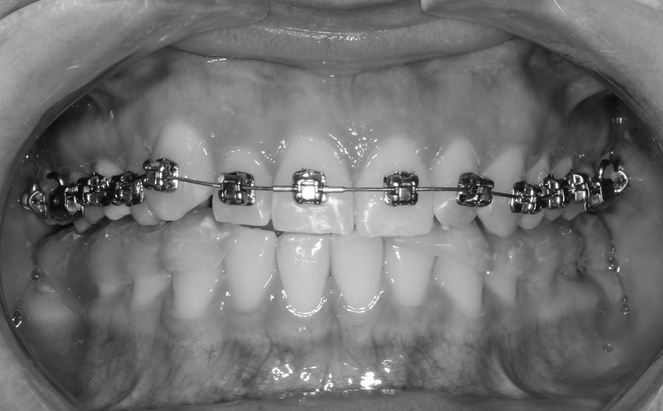

After three months, the bracket system was fixed to the lower row of teeth (Fig. 7) and fixation of photocomposite overlays, which in this clinical case were located in the area of teeth 1.6, 2.6, wearing of the splint was completed at this stage (Fig. 8).

Fig. 7. The stage of applying the brace system to the teeth of the lower jaw